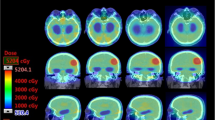

With approval from our institutional review board, we studied nine patients who had previously been diagnosed with brain metastases and were treated at our institution with standard, two-beam opposed lateral WBRT. Computed tomography (CT)-based treatment planning images were available for each of these patients, and these data sets were used to repeat the treatment planning process using intensity-modulated and volumetric-modulated arc techniques. Four new plans were created for each patient: (1) four-beam IMRT (Fig. 1), (2) seven-beam IMRT, (3) 13-beam IMRT, and (4) VMAT (single arc technique) and multiple normal tissue constraints were placed on identified organs at risk within the patient image sets (Table 1). The number and arrangement of beams were selected in order to provide homogeneous dose distribution to the PTV while also understanding clinical applicability of devised plans. Normal tissue structures were manually contoured by a single individual using Pinnacle 3 treatment planning software, version 8.1 s. These structures included the parotid glands, external ears, internal auditory canals, cochlea, eyes, lenses, optic nerves, brain (to the bottom of the medulla), skull, skin, and soft tissue of the scalp (defined as skin minus 0.5-cm depth). All four created plans were then compared to the original opposed lateral plan with respect to multiple normal tissue dose parameters. Normal tissue constraints were determined using the As Low As Reasonably Achievable principle. If normal tissue constraints (Table 1) were not able to be satisfied due to the fact that decreasing tissue dose would sacrifice PTV coverage, we ensured all critical structures received the same or lower dose than they did in the opposed lateral plan. IMRT plans included a mixture of coplanar and vertex beams set to avoid entry or exit through eyes, ears, and mouth, when possible (Table 2). The PTV was defined as whole brain plus a 0.5-cm uniform 3D expansion. The prescribed dose was 37.5 Gy in 15 fractions; volumetrically for the IMRT and VMAT plans and to mid-plane for the opposed lateral plan. All plans were optimized to achieve equivalent uniform PTV coverage while maintaining an equal or lower dose to lenses, eyes, optic nerves, brainstem, internal auditory canals, and bilateral cochlea as compared to the opposed lateral technique. The IMRT cost function was adjusted manually in each case, as needed, to meet treatment planning objectives and weighted such that priority was given to PTV coverage followed by objectives to reduce dose to the scalp, parotid glands, and external auditory canals. Cochlear dose could not be reduced in this setting due to its inclusion/close proximity to the PTV (brain + 0.5 cm). Once all of the new plans were complete, multiple dose–volume histogram (DVH) parameters for the PTV and organs at risk were compared for statistical and clinically meaningful reductions in dose and PTV coverage. Parameters assessed included mean dose, minimum dose, maximum dose, V5, V10, V15, V20, and V30 for each region of interest.

Regarding scalp dose, improved sparing was seen for low, intermediate, and high doses (V5, V10, V20, and V30) with the four- and 13-beam IMRT plans. The seven-beam IMRT plan improved intermediate and high doses (V10, V20, and V30) while only high doses (V20 and V30) were reduced in VMAT plans (Table 4). Compared with the OL technique, the four-field IMRT plan reduced the mean dose to the scalp the most (20.8 % reduction) followed by the 13-field (−19.8 %), seven-field (−13.8 %), and VMAT (−4.8 %). Depending on the DVH parameter, IMRT/VMAT reduced scalp dose by 10–70 %, external ear/auditory canal dose by 2–96 %, and parotid gland dose by 3–31 % (Fig. 2).